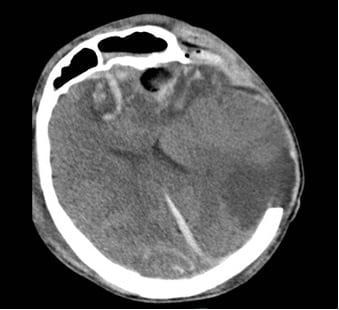

Người bệnh G.A. (nam, 28 tuổi) nhập viện trong tình trạng hôn mê sâu, phải thở máy qua nội khí quản. Hình ảnh CT scan sọ não ghi nhận tình trạng dập não xuất huyết rải rác, phù não lan tỏa, nguy cơ tử vong luôn ở mức cao. Người bệnh được điều trị tích cực tại Đơn vị Hồi sức Ngoại khoa – Khoa Gây mê Hồi sức.

Hình 1. Phim CT não người bệnh G.A. ngày 06/01/2026 cho thấy dập não xuất huyết nhiều nơi, phù não lan tòa dù đã được mở sọ giải ép tối đa.